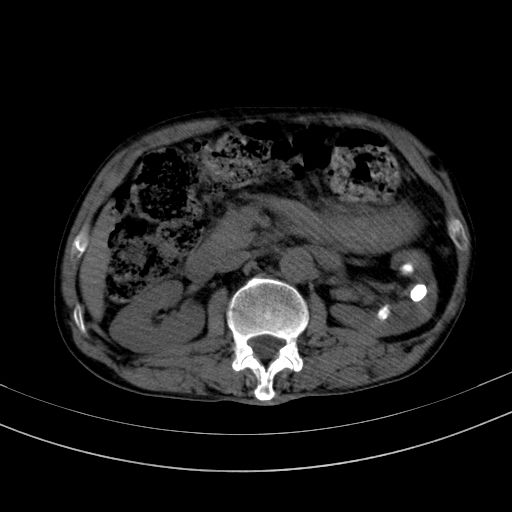

以下是引用37度在2010-1-9 14:37:00的发言:[br]1.双肾囊肿,左肾积水结石,.胆总管轻度扩张;[br]2.病灶在腹膜外,考虑纤维瘤。

以下是引用dyqct在2010-1-9 17:56:00的发言:[br]考虑:1.双肾囊肿,左肾积水结石、旋转不良。[br] 2.右侧腹直肌血肿或纤维瘤。[br]肠道准备不好。做个增强。